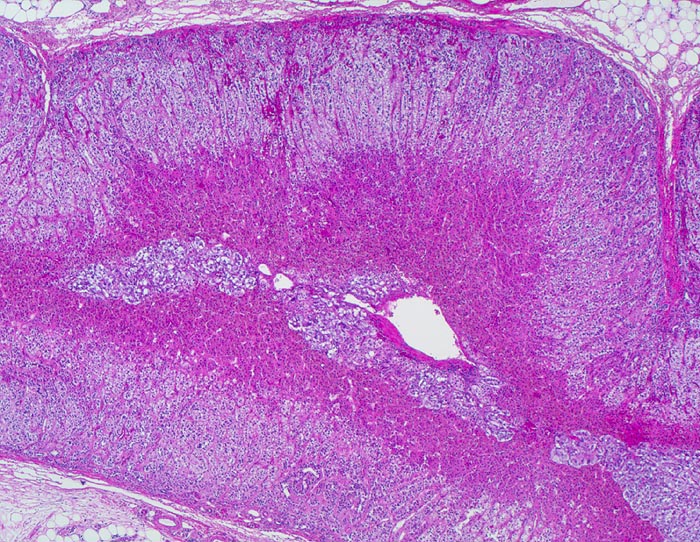

normale Nebenniere

Schichten der Nebenniere:

Zona fasciculata: Helles Areal der Nierenrinde. Bildungsort für Glucocorticoide.

Zona reticularis: Dunkles Areal angrenzend an das Nebennierenmark. Bildungsort für Sexualhormone.

Nebennierenmark

Das kombinierte Gewicht beider Nebennieren bei gesunden Erwachsenen Frauen und Männern beträgt ca. 8g. Die Dicke der normalen Nebennierenrinde beträgt 1mm (0.7-1.3mm).